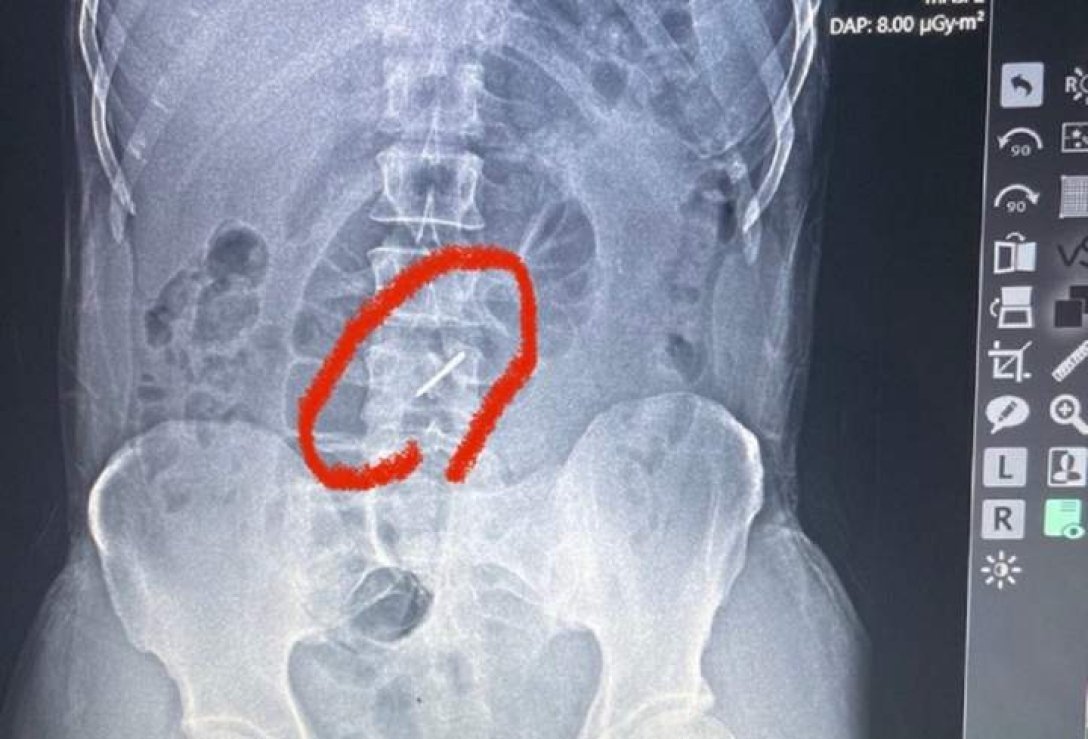

Військовослужбовець ЗСУ майже три тижні воював на передовій зі зламаним хребтом. 44-річний чоловік навіть не підозрював, що у його хребті застрягла «стрілка» від касетної бомби.

Як розповів лікар військово-польового госпіталю Тарас Кобза, коли бійця скерували на рентген, аби чітко встановити причину болю, то лікарі були шоковані побаченим на рентгенівському знімку.

«Під час обстрілу елемент касетної бомби, так звана «стрілка», потрапила у ліве підребер'я, зламала два хребці у поперековому відділі хребта і застрягла у хребті. Уламки зламаних хребців могли ушкодити нерви, судини, але, на щастя, цього не сталося. Боєць прийшов у польовий госпіталь своїми ногами і навіть не підозрював, що у його хребті застряг елемент касетної бомби», – каже Тарас Кобза.

За його словами, боєць потрапив під обстріл ще 13 липня, а до шпиталю звернувся лише на початку серпня. Він практично три тижні воював зі зламаним хребтом. Наразі бійця із зони бойових дій відправили в одну з лікарень у більш безпечний регіон, де він проходитиме лікування.

«Стрілка» касетної бомби, що зламала бійцю хребці, влучила у підребер'я, а у тому місці у чоловіка є кілька родимок. Вона зробила прокол всього на 1 мм, тож чоловік його навіть не зауважив. Його виявили медики під час ретельного огляду пораненого.